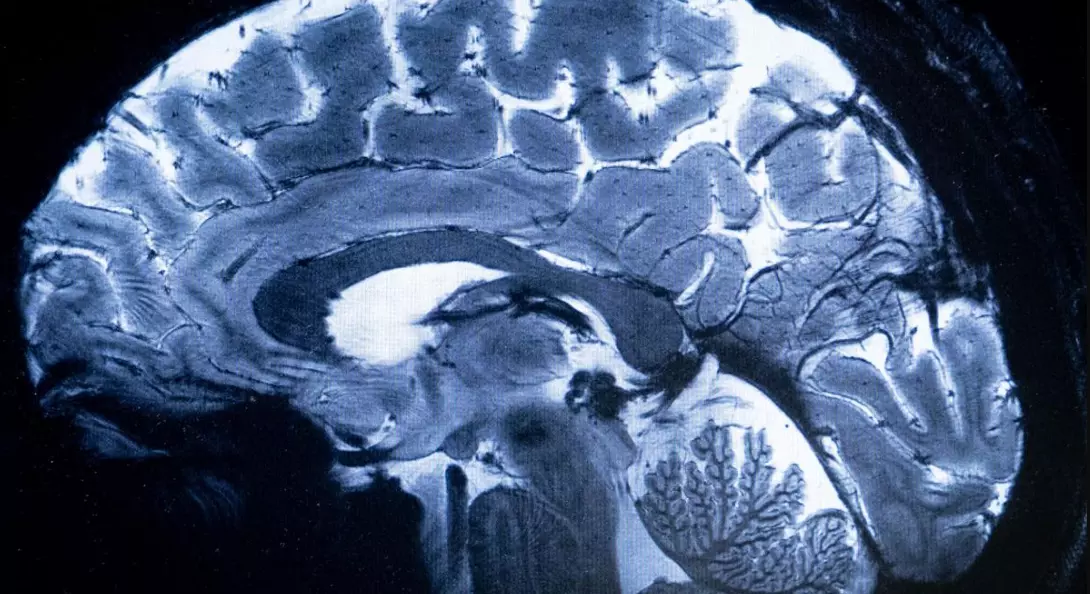

With another fatality in Malappuram, Kerala’s toll from amoebic meningoencephalitis has risen to five since August, prompting the state to step up preventive and treatment measures.

Malappuram: One more person succumbed to amoebic meningoencephalitis, a rare and often fatal brain infection, in Kerala on Monday, taking the total toll since August to five in the state. A 54-year-old woman, hailing from Vandoor in this district, was the latest victim of the infection.

In view of the situation, the Kerala Health Department recently issued special guidelines for the treatment of amoebic meningoencephalitis, the rare brain infection caused by free-living amoeba in contaminated waters.

According to health officials, amoebic meningoencephalitis is primarily contracted through swimming or bathing in contaminated water. A total of 42 cases have been reported across Kerala this year, they added.